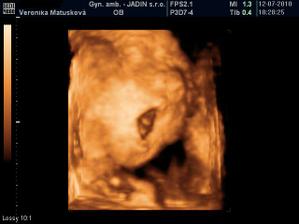

Adamko - 3D/4D

No tot vidno, že je náš syn, sa hanbil a hanbil až sa ukazovať nechcel....ale niekedy sa to podarilo, aj ked to nie je nejaká sláva. Pán doktor nám potvrdil chlapčeka, tak sme radi, vajká ukazoval ako len vedel len toho pipíka stále schovával. Ale je to za nami, pán doktor nás pekne popísal čo je kde, poodmeral nás a povedal, že je všetko v poriadku.